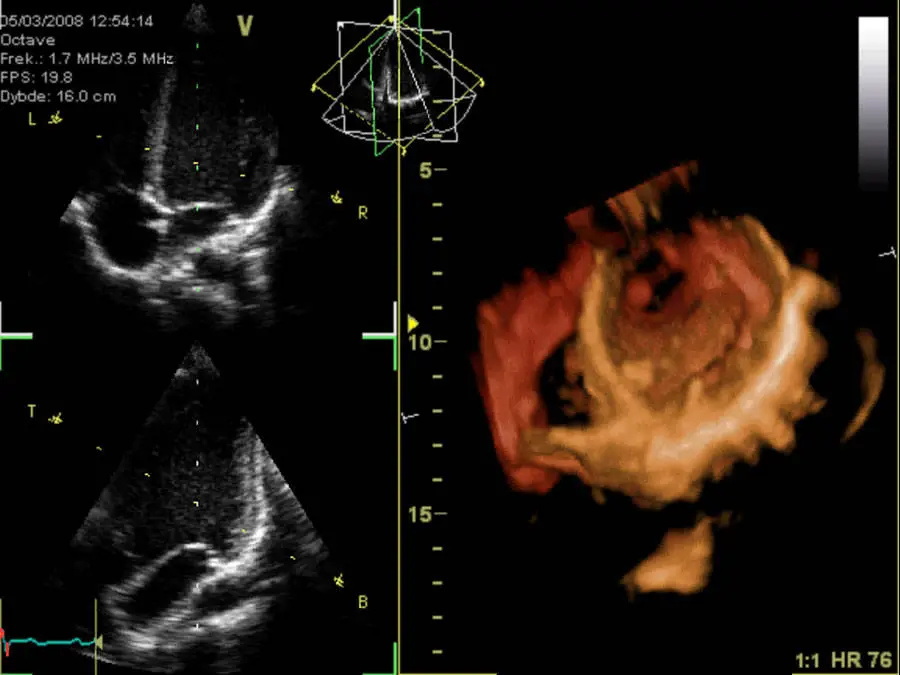

- Fig. 1 Il cuore visto dall'pice

- By Kjetil Lenes - Own work, CC BY-SA 3.0, https://commons.wikimedia.org/w/index/?curid=3705964